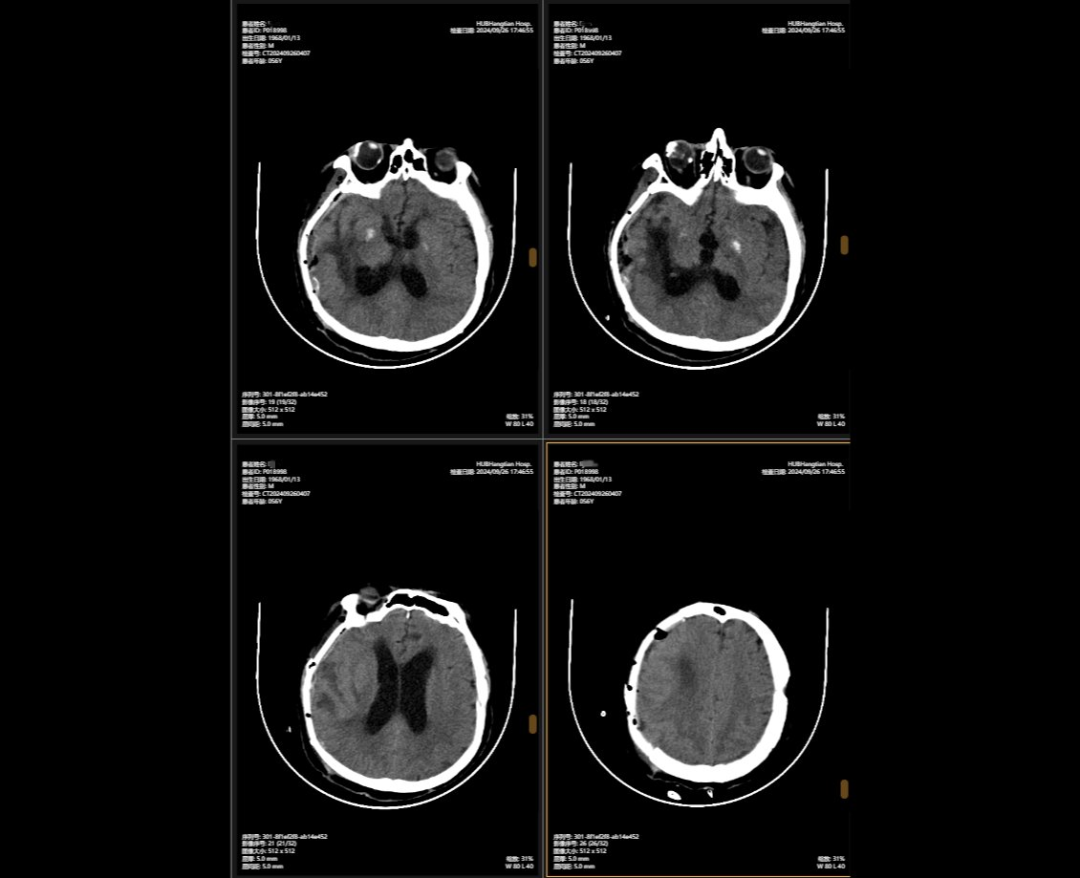

2024年5月,56歲的李先生(化名)不幸遭遇嚴(yán)重車禍,當(dāng)場昏迷,生命垂危。他被緊急送往湖北航天醫(yī)院后,檢查結(jié)果讓所有人心頭一緊:他的頭部受到嚴(yán)重撞擊,不僅有多處出血,腦組織也有挫傷,甚至連呼吸心跳的“總司令部”——腦干都受了傷。除此之外,還有顱骨、頸椎和多處肋骨骨折,情況萬分危急。

李先生頭部的多處損傷就像一顆顆“炸彈”,隨時可能危及生命。航醫(yī)神經(jīng)外科團(tuán)隊接診后,面對如此復(fù)雜的顱內(nèi)損傷,神經(jīng)外科主任陳義勇當(dāng)機(jī)立斷,一方面做好周密的手術(shù)準(zhǔn)備,一方面迅速展開多學(xué)科會診,多學(xué)科團(tuán)隊緊急集合,反復(fù)協(xié)商探討,一同制定了詳盡手術(shù)方案。手術(shù)方案確認(rèn)后,神外團(tuán)隊爭分奪秒,第一時間為李先生實施了顱內(nèi)多發(fā)血腫清除術(shù)+右側(cè)開顱顱內(nèi)減壓+去骨瓣減壓術(shù)+左側(cè)硬膜外血腫清除術(shù)+矢狀竇破裂止血術(shù)。手術(shù)過程中,醫(yī)生們精準(zhǔn)操作,成功止住了出血,最大限度地保護(hù)了正常腦組織,為李先生贏得了生的希望。

李先生的病情穩(wěn)定后,神外團(tuán)隊緊繃了數(shù)周的神經(jīng)終于得以松弛,他們隨即為他制定了顱骨缺損與腦積水治療方案,2024年9月,李先生接受了顱骨缺損修補術(shù),“修補”之前取下的頭骨,保護(hù)大腦,解決顱內(nèi)壓力不穩(wěn)問題,術(shù)后他的神經(jīng)紊亂癥狀明顯改善;三個月后,神外團(tuán)隊繼續(xù)施行腦室-腹腔分流術(shù),通過植入的分流管,解決了腦積水問題,讓腦壓恢復(fù)正常。

顱骨缺損修補術(shù)前術(shù)后對比